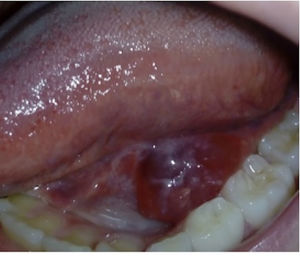

Presentamos el caso de una niña de 9 años remitida a nuestro servicio de cirugía pediátrica por una tumefacción recurrente en la base de la lengua de 5 meses de evolución. La exploración reveló una tumefacción con contenido líquido (fig. 1). El análisis histopatológico confirmó la presencia de un quiste de retención mucosa unilocular asociado a sialoadenitis crónica, atrofia acinar, ectasia ductal e infiltrado linfoplasmocitario. La resonancia magnética mostró quistes pequeños bilaterales en las glándulas sublinguales compatibles con ránulas simples y un aspecto multiquístico en las glándulas parótidas sugerente de lesiones linfoepiteliales asociadas al síndrome de Sjögren (SS) (fig. 2). La analítica reveló elevación de anticuerpos antinucleares (1:640), niveles altos de anticuerpos anti-SSA (>240U/mL) y elevación leve del factor reumatoide (32UI/mL). Otras pruebas, como la enzima convertidora de angiotensina sérica, el proteinograma, subclases de inmunoglobulina, niveles de complemento, crioglobulinas y anticuerpos anti-dsDNA, anti-SSB y anti-U1RNP, estaban dentro del rango normal. El test de Schirmer confirmó un déficit grave en la producción de lágrimas (<5mm). Posteriormente, la paciente desarrolló síndrome seco, que mejoró con tratamiento sintomático.